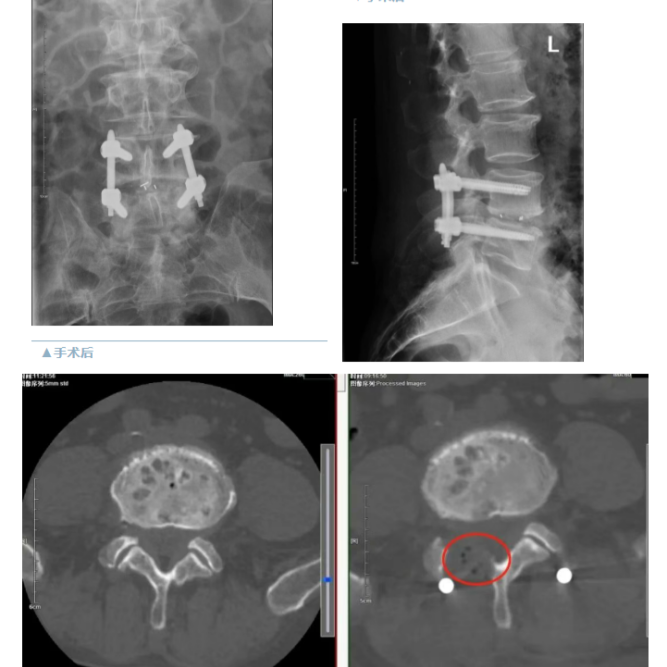

精准切除病变的腰椎间盘,彻底解除神经根和硬脊膜的压迫,完成椎间植骨融合,经皮椎弓根置入内固定系统。整个手术过程出血量极少,视野清晰,操作精准。

“镜下看得特别清楚,神经保护得很到位。”院长助理脊柱微创骨科主任陈晋伟介绍,“传统开放手术需要剥离椎旁肌肉,创伤大;而Endo-PLIF完美保留了肌肉附着点,这是患者术后能够快速恢复的关键。”